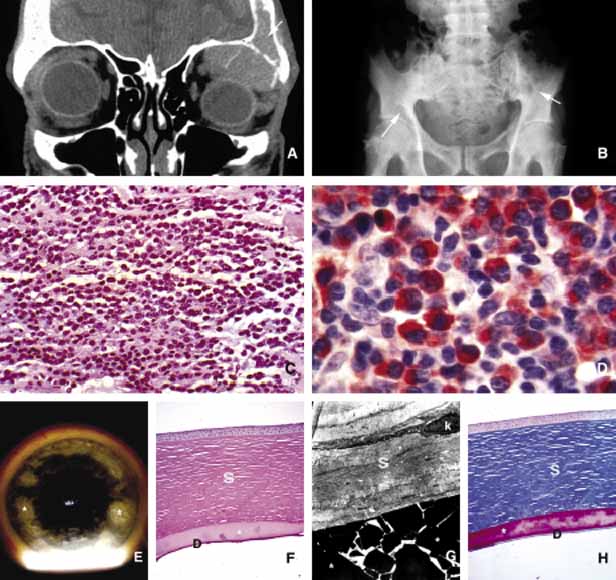

Another issue to deal with in an injured orbit is the development of hematoma, hematic cyst, and cholesteotoma. Hemorrhage in the orbit may occur spontaneously without any physical exertion in healthy individuals. Although terminology is not very strict, hematoma usually refers to a localized collection of blood within orbital soft tissues that develops secondary to trauma. When the blood collection within the orbit becomes organized and surrounded by a thin pseudocapsule, it is known as a hematic cyst31 (Fig. 4). If the hemorrhage develops within an existing lymphatic or vascular tumor, these lesions are known as blood cysts or “chocolate” cysts.32

Fig. 4 Hematic cyst. Axial CT scan (A) showing a large superiorly located, well-circumscribed hematic cyst (hc) presenting as an homogeneous low-density image. Intraoperative photograph of the same case shows dark brown hematic cyst. (B). C and D show the gross and histopathologic appearance of the hematic cyst respectively. It is surrounded by a fibrous pseudocapsule (arrows) containing a mixture of cholesterol crystals, (cc), hematoidin crystals (HC), and other proteineceous debris.

Hematic cyst consists of a localized collection of blood surrounded by a nonepithelium-lined thin fibrous capsule.33 These lesions usually develop within 1 to 2 weeks of orbital trauma but chronic cases may occur up to 20 years after orbital injury.34,35 They may reach to a size causing proptosis, extraocular motility disturbance, compression on the globe and optic nerve, that can easily be detected with ultrasonography, CT, or MRI. Hematic cysts may develop within the muscle cone or in the extraconal orbital locations.33–36 These cysts are lined by fibrovascular tissue at the periphery and contain degenerated erythrocytes, protein debris, and cholesterol crystals. In many instances the thin nonepithelial lining is adherent to the adjacent structures with fibrous tissue.

Cholesteatoma is another cystic lesion that is confined within a “pseudowall” without an epithelial lining.37 Cholesteotomas are usually located in the superior lateral orbit within the lacrimal gland fossa. Imaging studies may show a cystic, semi-cystic, or a solid lesion within the diploe of the bone or within the orbital soft tissues, with or without erosion of the adjacent bone.38 Histopathologically the lesion is composed of cholesterol clefts, hemosiderin, and hematoidin granules, other blood breakdown products and fibrin surrounded by a mixed lymphohistiocytic infiltrate and multinucleated foreign body giant cells.39

On imaging studies these lesions appear as unilocular rounded masses with destruction of the adjacent frontal and zygomatic bones. Although bone involvement in general implies malignancy, the sclerosing character of the bony destruction in choleosteoma, which is best seen in bone window images, favors a benign lesion. Although bone destruction also makes one think along the lines of metastatic tumors, one should also consider benign lesions such as brown tumor, aneurysmal bone cyst, and ruptured dermoid. Multiple cuts of the frontal bone should be examined to rule out the possibility of intracranial extension.